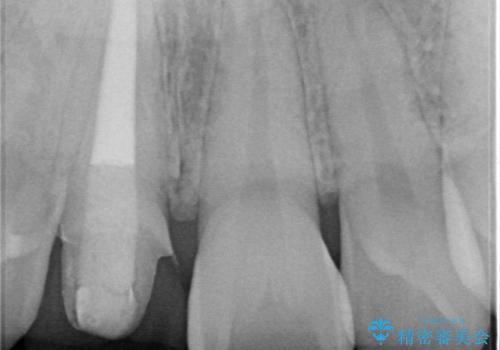

根管の充填物も不十分だったため根管治療からやり直しオールセラミッククラウンで治療を行いました。

- 297,000円(精密根管治療11万円+ファイバーコア2万2千円+仮歯1万1千円+オールセラミッククラウンスペシャル15万4千円)費用は治療当時の料金となります

根管の中が空洞のままで被せ物と歯のきわも合っておらず適合が悪い状態でした。根尖部付近にはパーフォレーションリペア修復の痕がありました。バイオシーシーラーを使用しシングルポイント法で充填しました。空洞があると細菌が増える環境になってしまうので、根管治療からやり直し、緊密に充填しました。被せ物の見た目も大変満足していただけました。